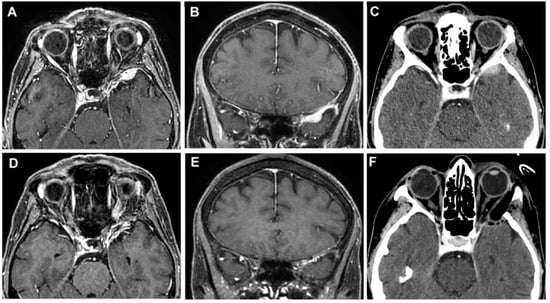

3.3. Clinical Cases

3.3.1. Case 1

3.3.2. Case 2

3.3.3. Case 3